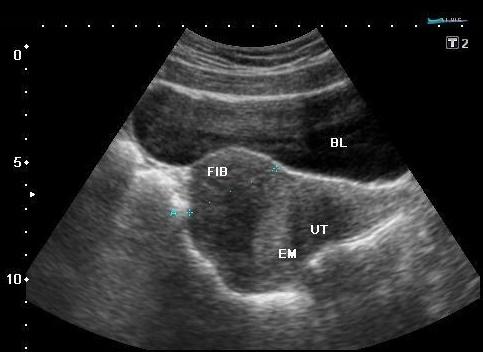

Leiomioma= (Fibroide, Myoma, Fibroma)

Tumor de tejido muscular

Comunes luego de los 35 años

Suelen ser múltiples

Se describen por su localización:

Submucoso - Intramural

Subseroso - Pedunculado

Submucoso (imagen)

Subseroso (imagen)

Intramural (imagen

Pedunculado (imagen)

Pueden tener calcificaciones

Dependiendo de su localización pueden causar infertilidad, presionar vejiga o recto, obstruir el canal vaginal.

Clinicamente causan irregularidad uterina y agrandamiento con sensación de presión pélvica y en ocaciones dolor.

Sangrado irregular

Menometrorragia o fuerte sangrado

*Menorragia es el problema clínico principal*

Myomas Uterinos

Por sonografía se ven:

Su apariencia dependerá del grado de degeneración ( de hipoecoicos – isoecoicos y ecogénicos)

Pueden interrumpir el contorno y tamaño uterino.